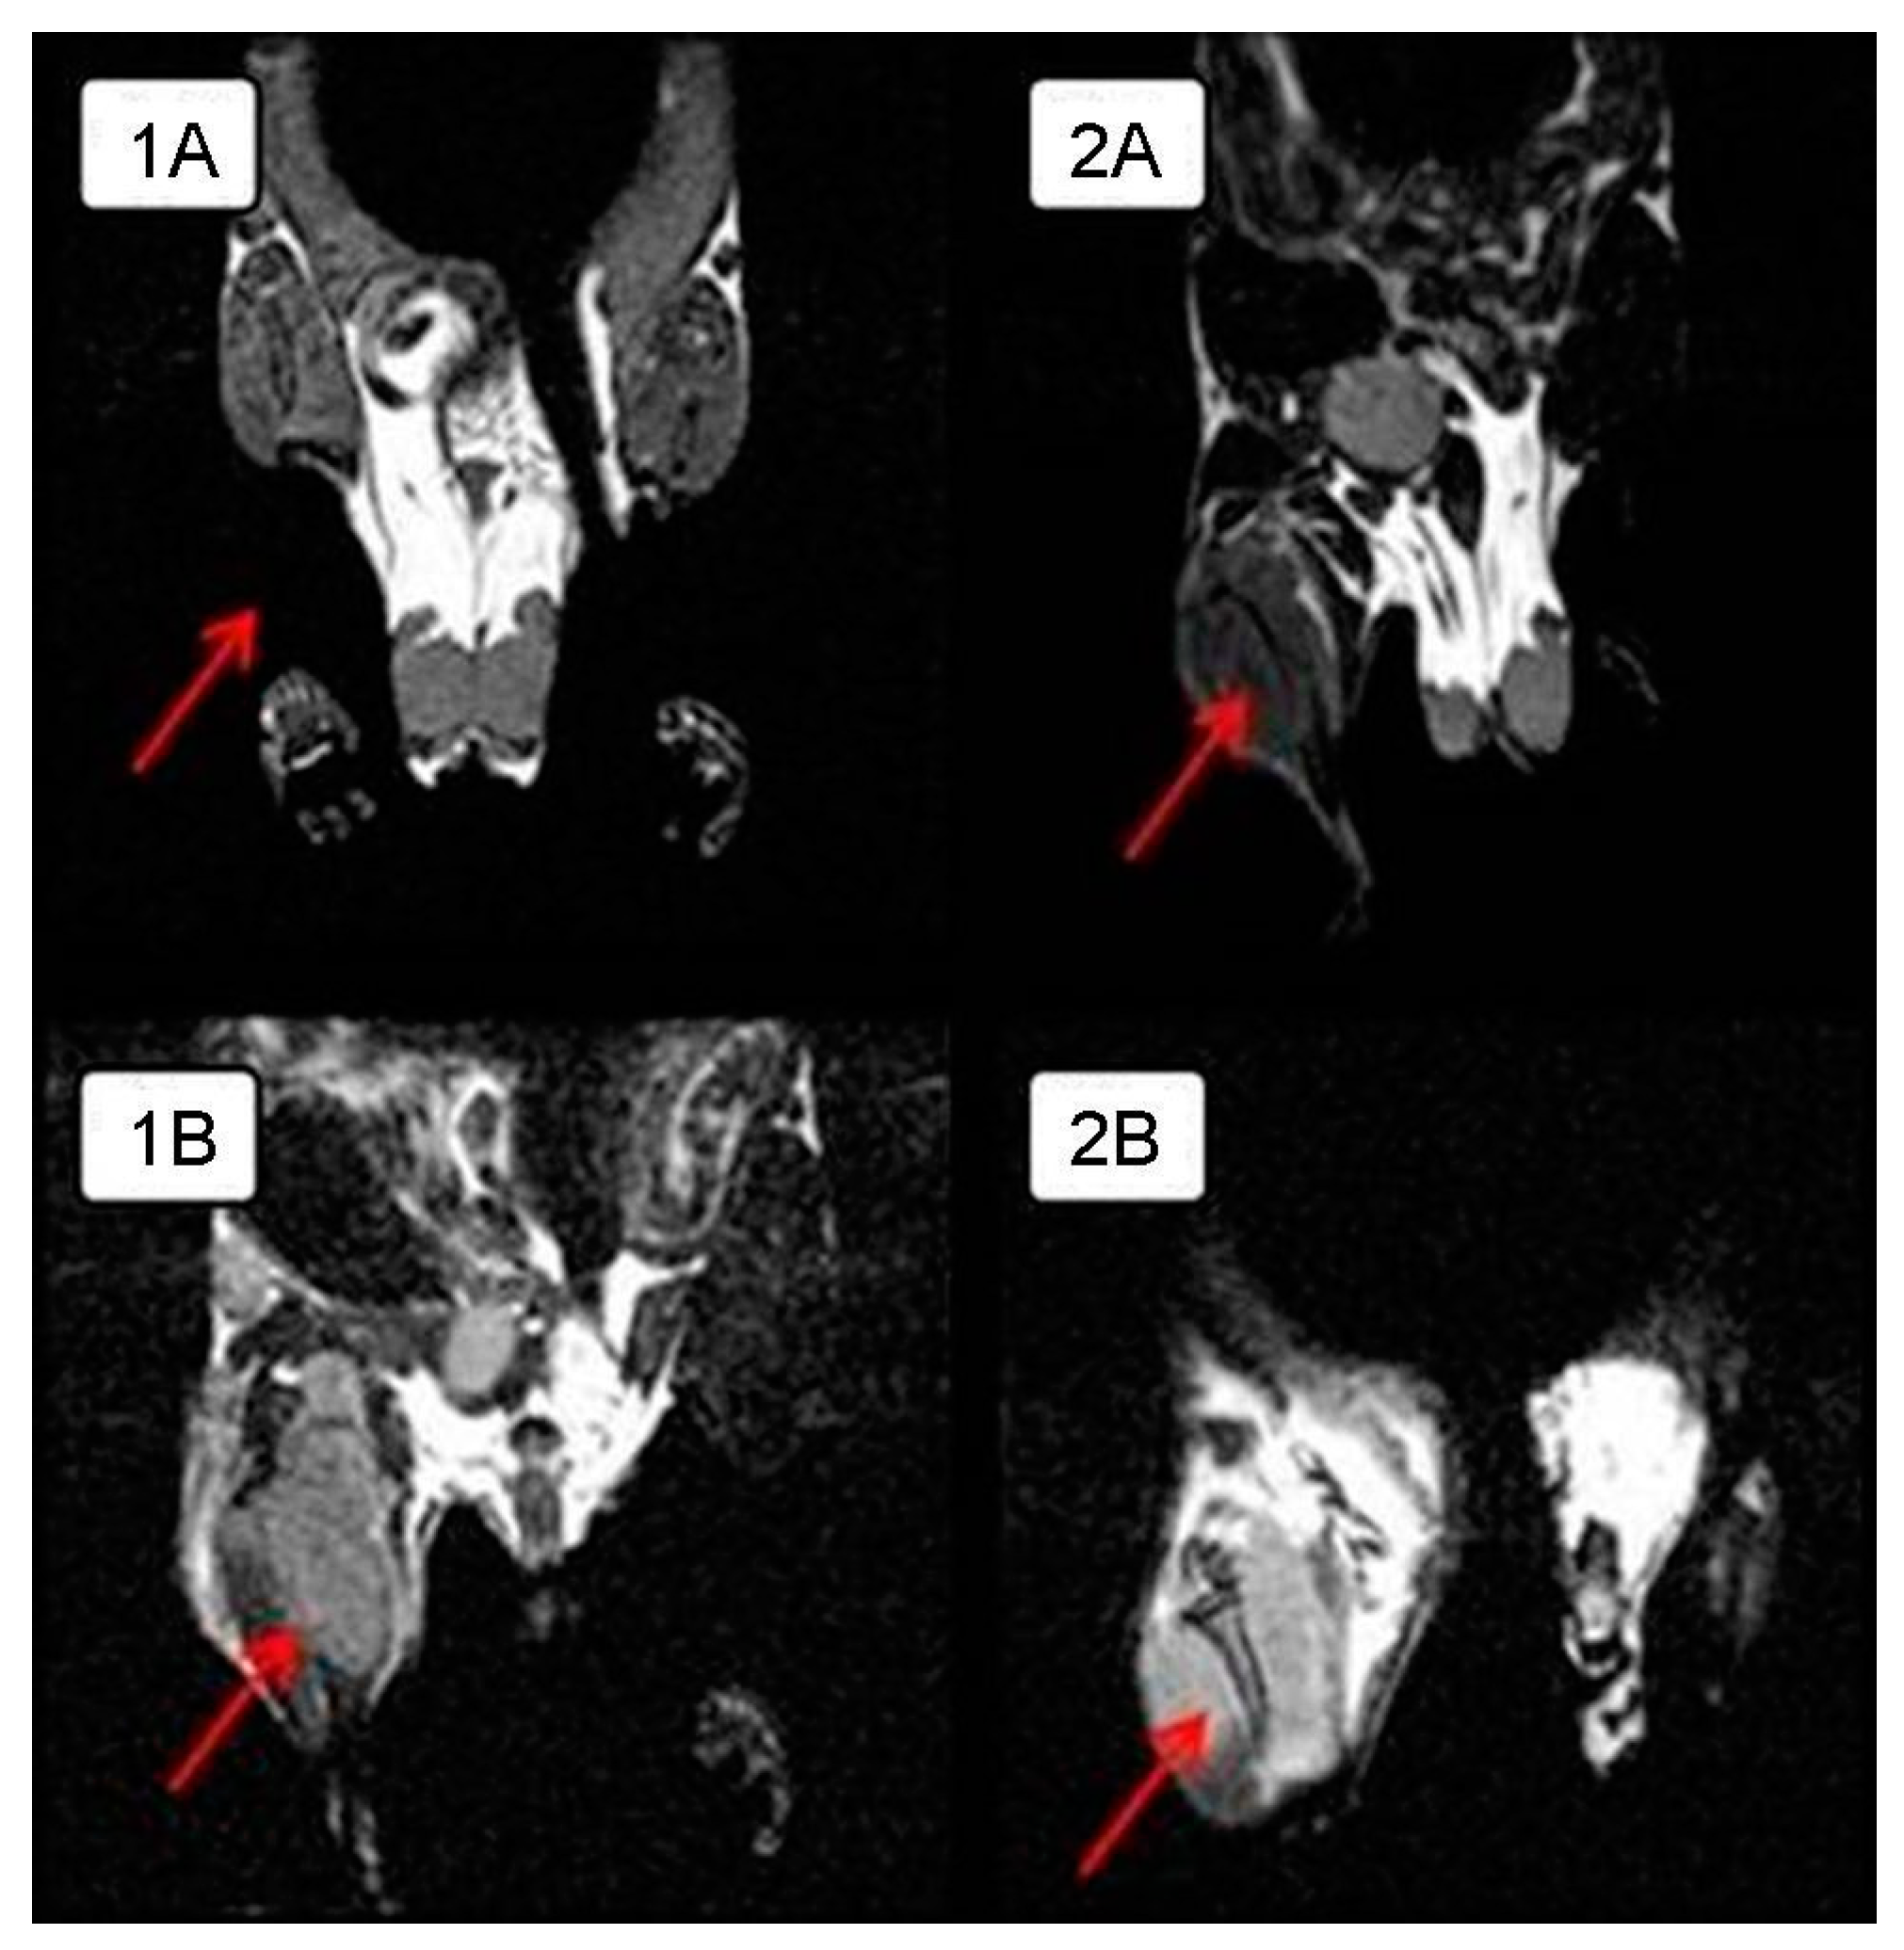

In order to visualize the tumor node growth in detail in the control group and compare the differences in the size of the intramuscular tumor with those of the experimental group animals, MRI was performed on day 28 of the experiment. The tumor is clearly visualized next to the normal tissues in a series of frontal sections on MRI. The obtained MRI data revealed almost complete tumor regression in one experimental mouse and a significant tumor reduction in another mouse compared to the control animals (Figure 2); intramuscular thigh tumor is clearly visualized next to the normal tissues.

Figure 2. MRI of intramuscular Krebs-2 solid tumor nodes in BALB/c mice in the frontal plane on day 28 from the onset of the experiment. Arrows indicate the tumor. A. Experimental mice receiving intratumoral injections of NDV/Altai/pigeon/770/2011 at a dose of 256 HAU per 100 μL for 5 days: (1A)—complete tumor regression compared to the control animals, (2A)—significant tumor reduction compared to the control animals; (1B,2B)—control mice treated with saline injections.